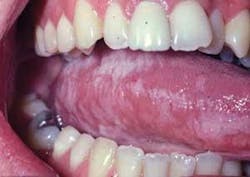

Significant microscopic characteristics: Microscopic appearances include hyperkeratosis with exophytic extensions of keratin that appear somewhat like hair. Many of the superficial keratinocytes show cytoplasmic clearing with perinuclear beading. Candida is often found on the surface of the specimen (see Figure 4).